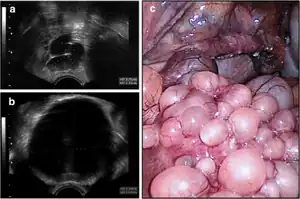

| Transvaginal ultrasound showed cystic formations in the areas of the right fallopian tube (a) and fundus uteri (b), (c); uterus (front) with right tube and right abdominal wall (background). | |